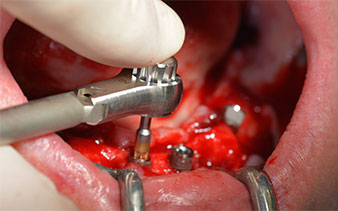

След отстраняване на частичното обеззъбяване в долната челюст, алвеоларният гребен е разкрит от 37 до 47.

Изходът на долночелюстния нерв е първоначално идентифициран като ограничена анатомична структура и, след това, кортикалната кост на гребена е загладена с прав наконечник и голям борер с розовиден профил  (Фиг. 4).

частично обеззъбяване

Фиг. 4